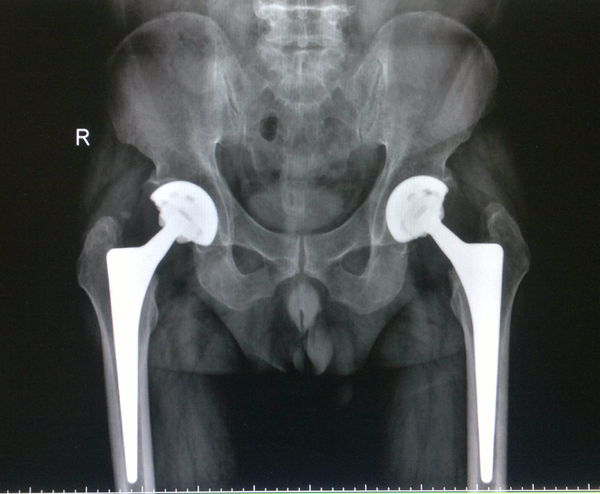

據(jù)了解,患者具有飲酒史30余年,并伴有強直性脊柱炎30余年,長期口服甾體類藥物,并有一定的成癮性。多年前行X線檢查顯示雙側(cè)股骨頭無菌性壞死,但由于經(jīng)濟及身體條件等因素致使手術(shù)遲遲沒有實施,以至于到后期患者不能行走,必須依靠輪椅出行,加之雙側(cè)大腿內(nèi)側(cè)內(nèi)收緊張,雙膝關(guān)節(jié)已不能伸直。

為了解除患者病痛,同時減輕其經(jīng)濟負(fù)擔(dān),武安市中醫(yī)院骨傷二科根據(jù)患者整體病情,多方位探究,制定了確實可行的治療方案。在征得家屬同意后,決定為患者實施科學(xué)的手術(shù)治療。因考慮到患者身體偏胖,且其強直性脊柱炎處于穩(wěn)定期,雙大腿內(nèi)收肌緊張,外展明顯受限,膝關(guān)節(jié)伸直不能。遂計劃先行雙側(cè)股內(nèi)收肌切斷,再行股骨頭置換術(shù)。根據(jù)預(yù)定的治療方案,在術(shù)中先行雙側(cè)內(nèi)收肌切斷術(shù),出血不多,于是行左側(cè)股骨頭置換術(shù),在切開皮膚及在進一步置換術(shù)中發(fā)現(xiàn)出血較多,考慮到病人長期服用止痛甾體類藥物所致,因此在術(shù)中決定先行一側(cè)股骨頭置換術(shù),待病人病情穩(wěn)定后再行另一側(cè)股骨頭置換術(shù),術(shù)后病人病情平穩(wěn),左下肢活動度改觀,膝關(guān)節(jié)可以伸直,經(jīng)過對癥治療后病情穩(wěn)定并予以拆線。后又行右側(cè)股骨頭置換術(shù),術(shù)后病人恢復(fù)較好,并逐漸在助力器支持下開始活動,病人恢復(fù)較滿意。